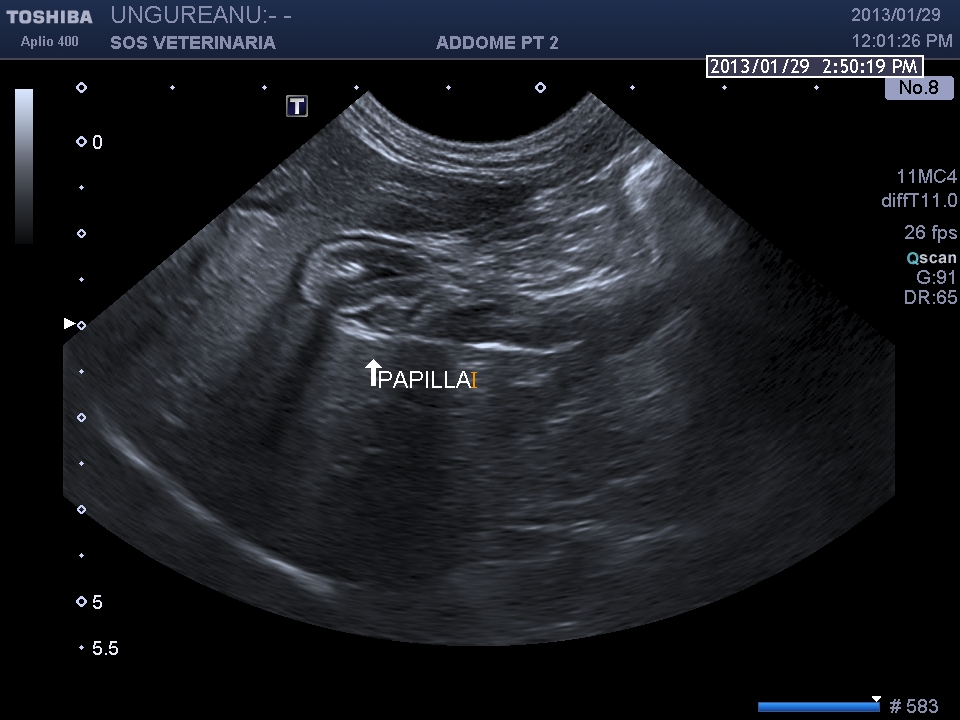

PROCESSO INFILTRATIVO DUODENALE E DELLA PAPILLA  (infiammatorio o neoplastico)

gatto comune europeo 9 aa ABC_8738

Le vie biliari del gatto hanno caratteristiche diverse rispetto al cane il dotto pancreatico principale raggiunge il coledoco  prima che questo defluisca nella papilla duodenale maggiore (nel cane lo sbocco e’ indipendente) ,inoltre il dotto accessorio  sfocia nella papilla minore ,un processo ostruttivo distale porta quindi a distensione  di entrambe le componenti  ,l’iperplasia della parete delle vie biliari  puo’ essere indicativa di flogosi o di cronicita’ dell’ostruzione  (in questo caso la parete e’ normale) ma come sopraesposto la diagnosi richiede spesso invasivita’ ,questo caso purtroppo  non ha seguito nessuna diagnosi ,il soggetto non ha risposto alla terapia cortisonica (l’unica che ha voluto tentare il proprietario) e antibiotica e si e’ perso nel foll’up, Una laparotomia esplorativa con campionamento del tessuto iperplastico  e coltura biliare era a mio avviso unica opzione possibile per una corretta diagnosi .

Il caso si mostra interessante sul piano dell’imaging che evidenzia la complessita’ delle vie biliari extraepatiche e pancreatiche dilatate.

Durante l’esame delle strutture biliari può venire identificata la papilla duodenale le cui dimensioni, nei gatti sani, variano dai 2,9 a 5,5 mm in larghezza ed una massima altezza di 4,0 mm, in sezione trasversa; nel cane le sue dimensioni sembrano essere maggiormente variabili, in relazione alle differenze di peso e di razza (Center S.A., 2009).”

scansione trasversale papilla

scansione sagittale paipilla